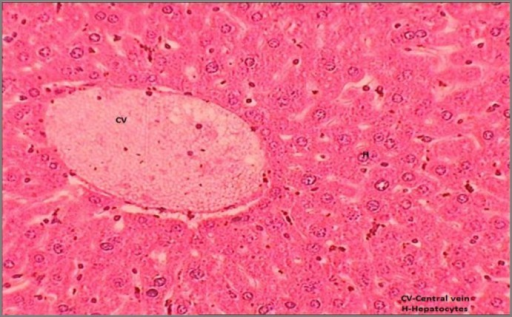

Transverse Section Of Liver Showing Normal Mice Liver W Open I